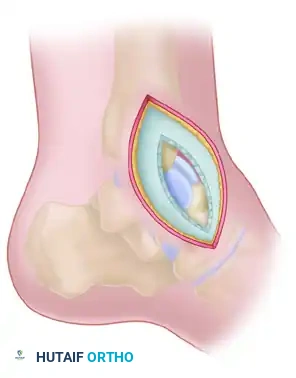

Medial Malleolar Osteotomy

If the body of the talus is extruded from the ankle mortise (Hawkins Type III or IV), or if posterior comminution prevents adequate visualization, a medial malleolar osteotomy may be required.

* Pre-drill the medial malleolus for subsequent screw fixation.

* Perform a chevron-type osteotomy directed toward the axilla of the medial clear space.

* Reflect the malleolus inferiorly on its intact deltoid hinge.